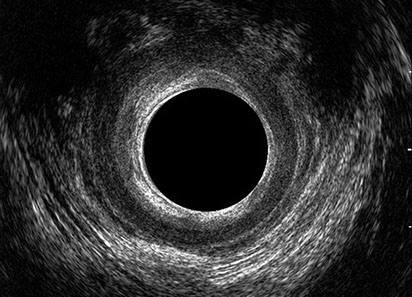

L’ecografia transanale è un esame diagnostico per immagini che consiste nell’introduzione di un trasduttore ad ultrasuoni. Le immagini qualitativamente migliori del canale anale sono ottenute usando un trasduttore rotante, montato in un manipolo rigido, che fornisce un’immagine a 360°. Con le apparecchiature più moderne è anche possibile ottenere immagini tridimensionali.

L’ecografia transanale permette di distinguere la sottomucosa che riveste il canale anale, lo sfintere anale interno, e lo sfintere anale esterno.

Le principali indicazioni all’esecuzione di tale esame sono lo studio dell’integrità delle strutture muscolari nei casi di incontinenza fecale, lo studio topografico dei processi settici perianali (ascessi e fistole) e lo studio dei processi proliferativi epiteliali (carcinoma anale).